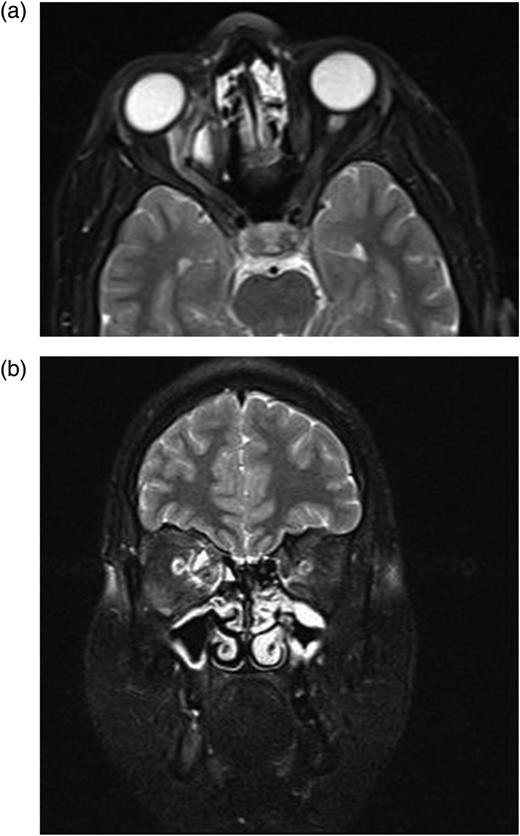

In the second postoperative month, the findings of ocular examination were the same. Control MRI revealed that there was a new small cyst in the intraconal space (Fig. 4a and b). Based on these findings, we planned the second operation via again medial transconjunctival orbitotomy. Peroperatively, we could not find remarkable cyst capsule. To prevent any inoculation, surgery area was washed with %0.9 hypertonic saline solution. Due to the postoperative edema, 80 mg systemic prednisolone was applied for 3 days. Systemic albendazole was applied twice a day for 2 months.

(a and b) After first operation, control MRI in the second postoperative month shows a small cyst displacing optic nerve laterally.